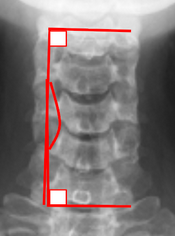

Image Type Cervical Spine X-Ray CT Scan MRI Scan Atlantodental Interval (ADI) Basion-Axial Interval Basion-Dens Interval (BDI) C2 Tilt C2–C7 Coronal Cobb Angle Cervical C2-7 lordosis C2-C7 Translation Chamberlain’s Line / McGregor’s Line Flexion-Extension George’s Line (Posterior Cervical Line) K-Line Interpedicular Distance (IPD) Occiput-C2 Angle Occipital Condyle–C1 Interval (CCI) Posterior Atlantodental Interval (PADI) Power’s ratio Sagittal Canal Diameter Sagittal Vertical Axis (SVA) Spinolaminar line Swischuk Line T1 Slope Torg/Pavlov Canal-to-Body Ratio